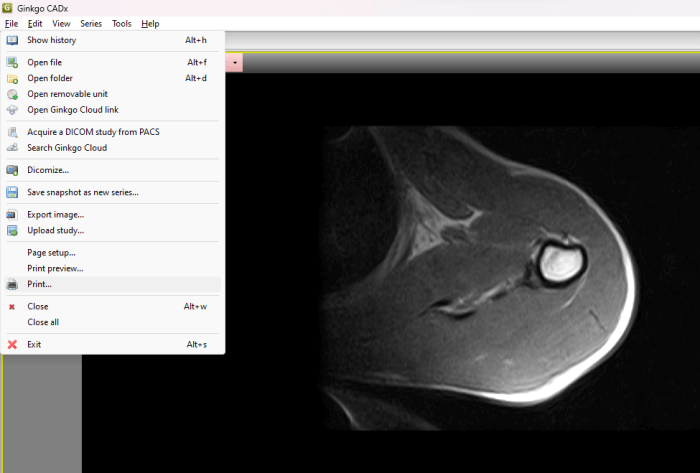

1] Ginkgo CADx

Ginkgo CADx is a free DICOM image viewer software that lets you save a DICOM image in PDF format. To convert a DICOM image into PDF format, first, you have to open it. The process to open a file in Ginkgo CADx is a bit different. Go through the following instructions to open a DICOM image file:

- Go to “File > Open file” and select the DICOM image from your computer. After that, you will receive a popup. Click Copy.

- Now, go to History. There, you will see the DICOM file. Double-click on it.

You will see multiple tools to analyze the image, like marking tools, ruler, angle measuring tools, etc. To convert the DICOM image into PDF, go to “File > Print.” After that, select the virtual printer, like Microsoft Print to PDF, and then click on the Print button. A new window will appear asking you to select a location to save the PDF file on your disk.

You can download Ginkgo CADx from ginkgo-cadx.com.